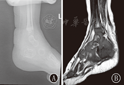

注:A:CT重建示左距骨骨质破坏,周围骨密度稍高;B:MRI示左侧距骨内可见片状长T1长T2信号,压脂像呈高信号,周围软组织肿胀明显 A:CT reconstruction showed talus bone destruction with mild osteosclerosis of bone around the lesion;B:MRI showed lamellar long T1 long T2 was observed in the left of talus,the fat was presented in high signal,and peripheral soft tissue was obvious swelling

注:A:X线显示右足距骨内可见透亮区,边缘欠清楚,踝关节周围软组织肿胀;B:CT示右距骨骨皮质骨小梁破坏,未见明显骨膜反应,周围软组织肿胀明显;C:MRI显示右距骨呈长T1长T2信号影,周围软组织肿胀 A:X-ray showed that there was a lucent area with indistinct edge in right talus bone,and peripheral soft tissue of right ankle was swelling;B:CT reconstruction showed that there was trabecular destruction without obvious periosteal reaction in right talus bone,and peripheral soft tissue was obvious swelling;C:MRI showed the intense T1 and T2 signal in talus bone and soft tissue masses around the lesion